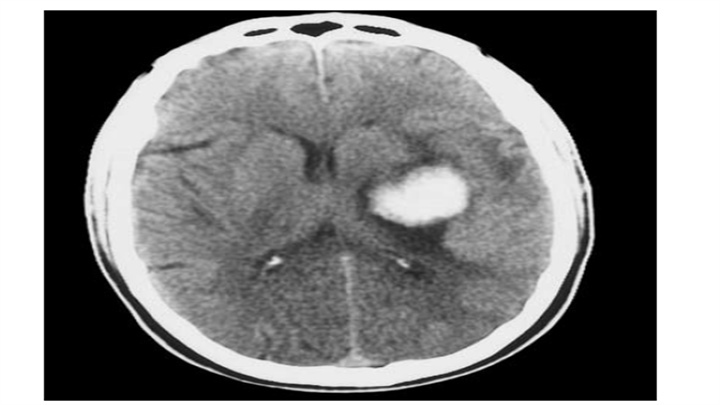

右顶叶血肿,高血压患者的自发性脑出血。